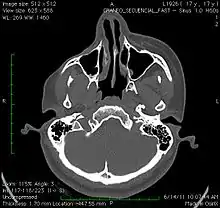

A 3D, soft tissue reconstruction of a CT scan of a 17-year-old girl with Parry Romberg syndrome.

CT scan3D bone reconstruction of a 17-year-old girl with Parry Romberg syndrome.